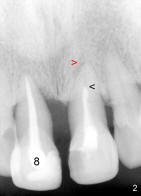

This article reports design of a simple semilunar incision for implant uncover to help form a natural-looking gingiva around anterior crown. A fifty-year-old lady has severe periodontal disease, complicated with endodontic lesion of the teeth #8 and 9 (Fig.1,2). #8 is extracted and Bicon 4.5x8 mm implant (Fig.3: I, Boston, Massachutte) is placed with bone expansion (Tatum Surgical, Clearwater, Fl) 1 year later . After RCT retreatment for #9 (compare Fig.2,3: black arrowheads), periapical radiolucency (Fig.2: red arrowhead) resolves (Fig.3).